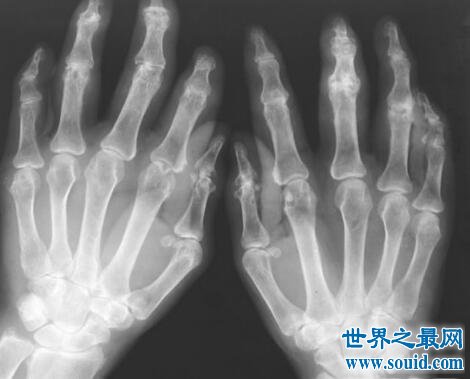

症状:目前来说,对于类风湿关节炎的病因还没有明确,可能跟内分泌、职业、代谢、病毒感染和遗传有关,是一种属于自身免疫炎性病症,该病多发在手、腕和足等小关节,且会反复发作,早期会出现关节红肿和出出行动不便,晚期的关节会出现僵硬畸形,有时伴有骨和骨骼的萎缩,甚至会致残,还会蔓延至全身病变,患者会有发热、疲乏无力、周围神经病变等现象。